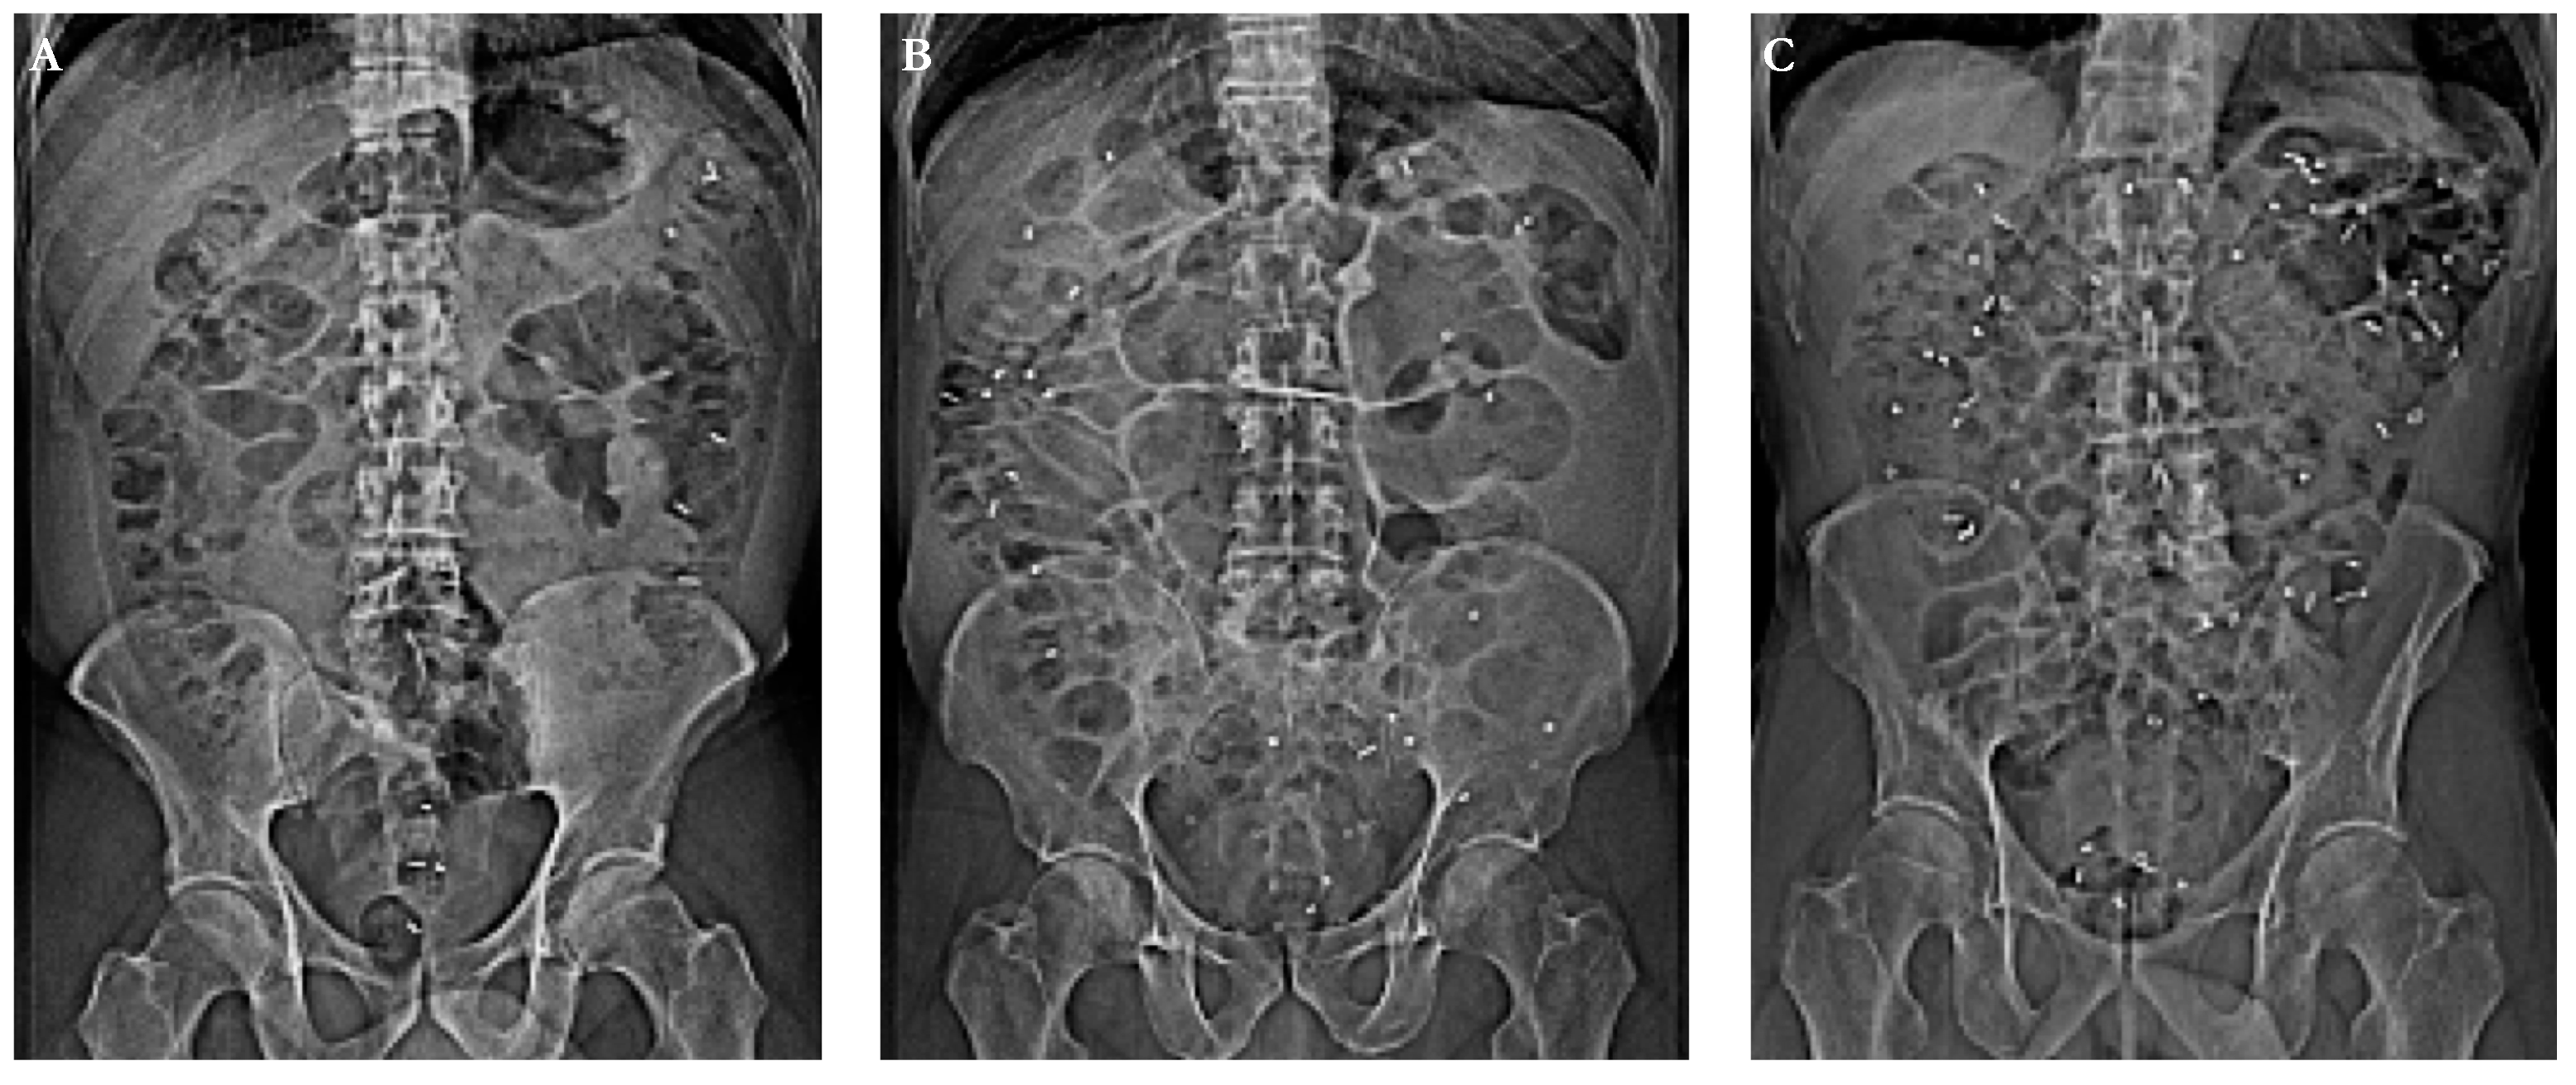

- Knudsen, K.; Fedorova, T.D.; Bekker, A.C.; Iversen, P.; Østergaard, K.; Krogh, K.; Borghammer, P. Objective Colonic Dysfunction is Far more Prevalent than Subjective Constipation in Parkinson’s Disease: A Colon Transit and Volume Study. J. Parkinson’s Dis. 2017, 7, 359–367. [Google Scholar] [CrossRef]

- Abrahamsson, H.; Antov, S.; Bosaeus, I. Gastrointestinal and colonic segmental transit time evaluated by a single abdominal x-ray in healthy subjects and constipated patients. Scand. J. Gastroenterol. Suppl. 1988, 152, 72–80. [Google Scholar] [CrossRef]